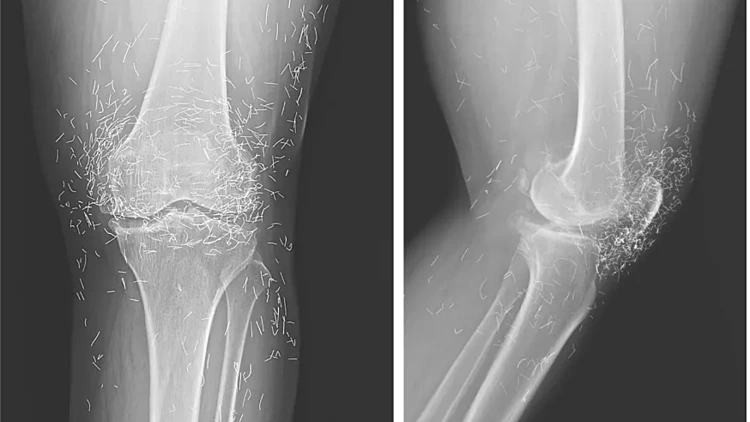

לאחר תקופה מממושכת במהלכה הכאב רק הלך והחמיר, האישה החליטה לחזור לבית החולים. בבדיקת רנטגן נמצאו עיבוי והסתיידות של החלק הפנימי של עצם השוק (טיביה) וזיזי עצם ברך, ממצאים אופייניים לאוסטיאוארתריטיס (דלקת מפרקים ניוונית). אך היה דבר אחר שהטריד את הרופאים – מאות חוטי זהב המשובצים ברקמות מסביב המפרק.

לפי הרופאים, החוטים הזעירים עלולים ליצור ציסטות, לנדוד בתוך הגוף ולפגוע ברקמות סמוכות. הרופאים הסבירו כי לטיפול דיקור בחוטי זהב אין תועלת מוכחת מדעית בטיפול בכאב, ולפרוצדורה יש סיכונים ממשיים.